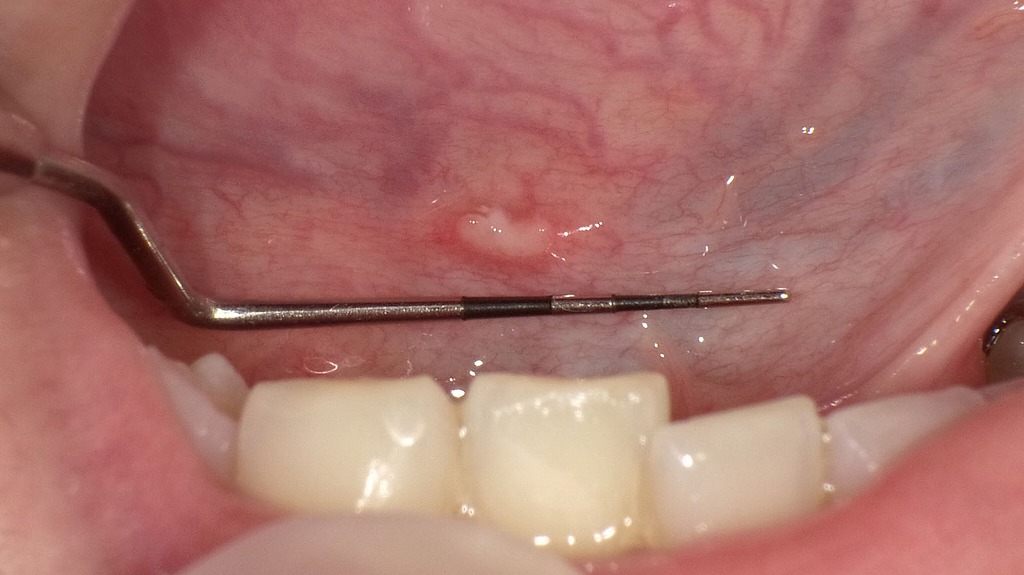

舌の裏側に、中央が白く周囲が赤く縁取られたアフタ性口内炎が認められます。舌の裏は動きが多く刺激を受けやすいため、食事や会話の際に痛みを感じやすい部位です。多くの場合、疲労やストレス、免疫力の低下などが誘因となり、1〜2週間程度で自然に治癒しますが、痛みが強い場合や長期間改善しない場合は歯科・口腔外科での診察が望まれます。

舌の裏側に、白っぽい潰瘍とその周囲の発赤がみられるアフタ性口内炎の所見です。食事や会話の際にしみるような痛みを伴うことが多く、ストレスや疲労、免疫力の低下などがきっかけで生じます。多くは1〜2週間ほどで自然に治癒しますが、痛みが強い場合や長引く場合は歯科・口腔外科での診察が推奨されます。